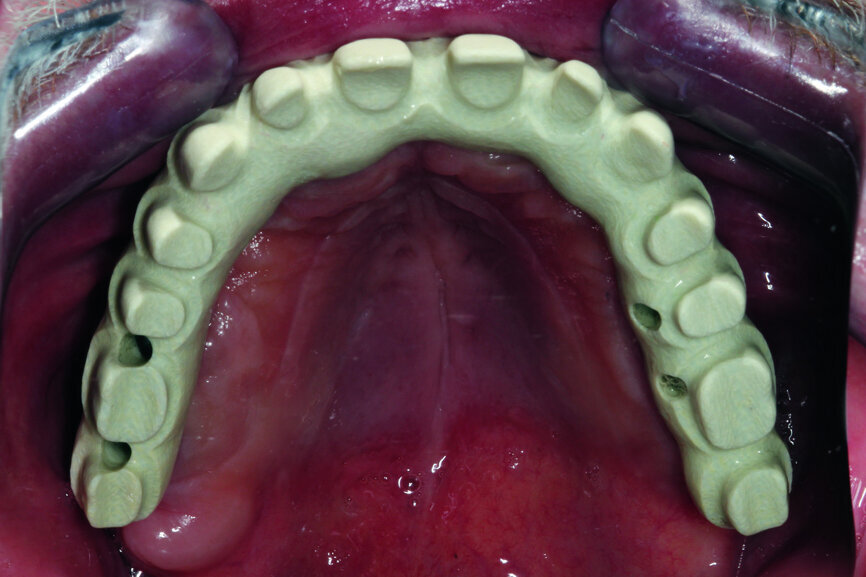

Fig. 12: Test of the construction within the oral cavity—visible opening for screws.

Fig. 21: Openings for screws are located before placing the crowns.